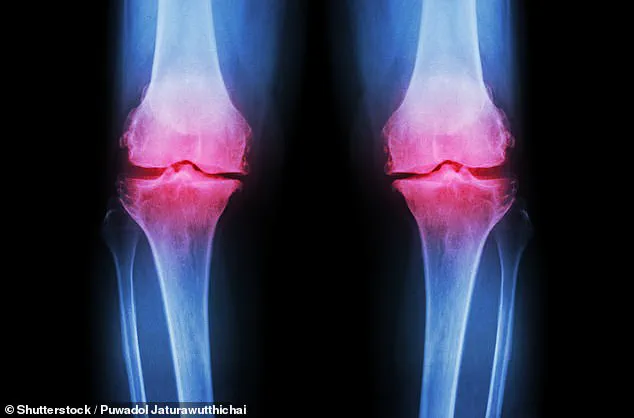

The condition develops when the protective cartilage at the ends of bones gradually breaks down over time, leading to pain, swelling, and increasing difficulty moving the joint as bone begins to rub against bone.

Over half of all cases are concentrated in the knees, and more than 100,000 people in the UK alone end up on NHS waiting lists for knee or hip replacement surgery each year.